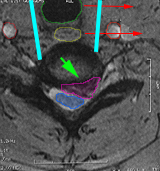

Πρόσθια αυχενική μικροχειρουργική δισκεκτομή σε ασθενή με αυχενική δισκοκήλη. Η τραχεία (πράσινο), ο οισοφάγος (κίτρινο) παρεκτοπίζονται αριστερά (κόκκινα βέλη) και για να δημιουργηθεί το κανάλι προσπέλασης στον δίσκο (κυανές γραμμές). Ο δίσκος αφαιρείται και κατόπιν εξαιρείται και η δισκοκήλη(μωβ). Οι καρωτίδες είναι οι δύο κόκκινοι κύκλοι εκατέρωθεν της προσπέλασης.